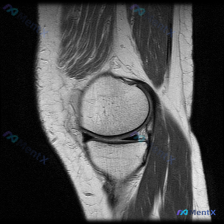

今天遇到一个挺有意思的病例,用户提示存在半月板异常,但只提供了单张膝关节MRI T1冠状位图像,整理一下分析思路分享给大家。 一、病例/影像基本信息 提供的单张膝关节MRI T1冠状位图像分析结果如下: 1. 骨骼结构:股骨远端、胫骨近端、腓骨近端轮廓清晰,骨髓信号正常,未见局灶性骨质破坏或异常信号...

今天整理一份很有代表性的膝关节MRI读片病例,和大家分享一下思路。这个病例最初是被怀疑有半月板异常,我们一起来看看实际情况。 病例影像基本信息 这是一份膝关节MRI冠状位T2加权图像,我们先梳理所有基础观察: 1. 股骨远端、胫骨近端骨髓信号正常,没有明显骨髓水肿 2. 半月板情况:内侧半月板体部形...